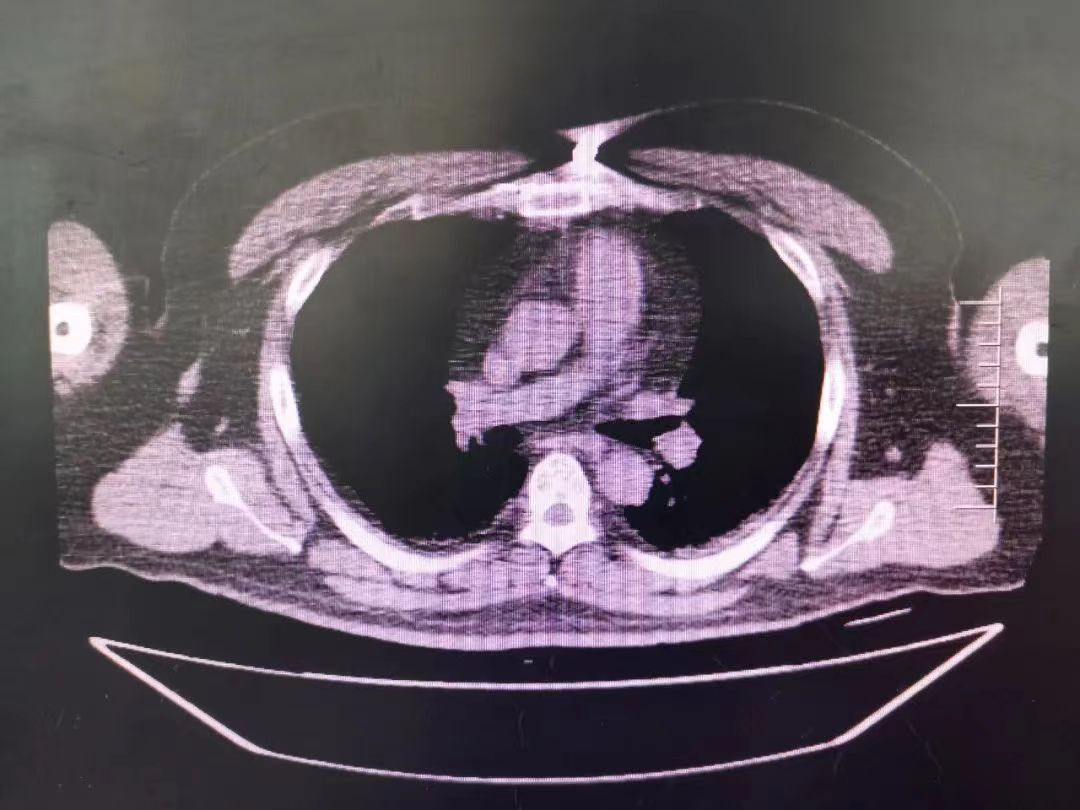

CT室門口,焦燥的家屬不停的走動著、等待著,看到醫生的到來,快速跑到醫生面前說:“醫生,快幫我看看,病人怎么樣”。陳醫生過去一看,一個體型偏胖的患者平躺在床上,一把剪刀齊根直插胸口觸目驚心,陳醫生不由眉頭一緊,轉身去看電腦CT影像 --剪刀斜著刺入胸骨,將胸骨完全穿透,刀尖距離心包約1-2mm,正下方是主動脈,大量心包積液?再一看,患者肥胖,脂肪組織多,不排除脂肪偽影。考慮患者血壓相對平穩,由于緊張導致心率快,立刻安撫患者,讓其保持安靜,盡量避免咳嗽,避免深呼吸和過多運動。隨即撥通了武小剛主任的電話:“主任,這有一位患者,銳器刺傷不排除已經損傷到心臟,病人目前血壓平穩”“嚴密監測患者病情變化,準備急診手術,我馬上到”武主任說。